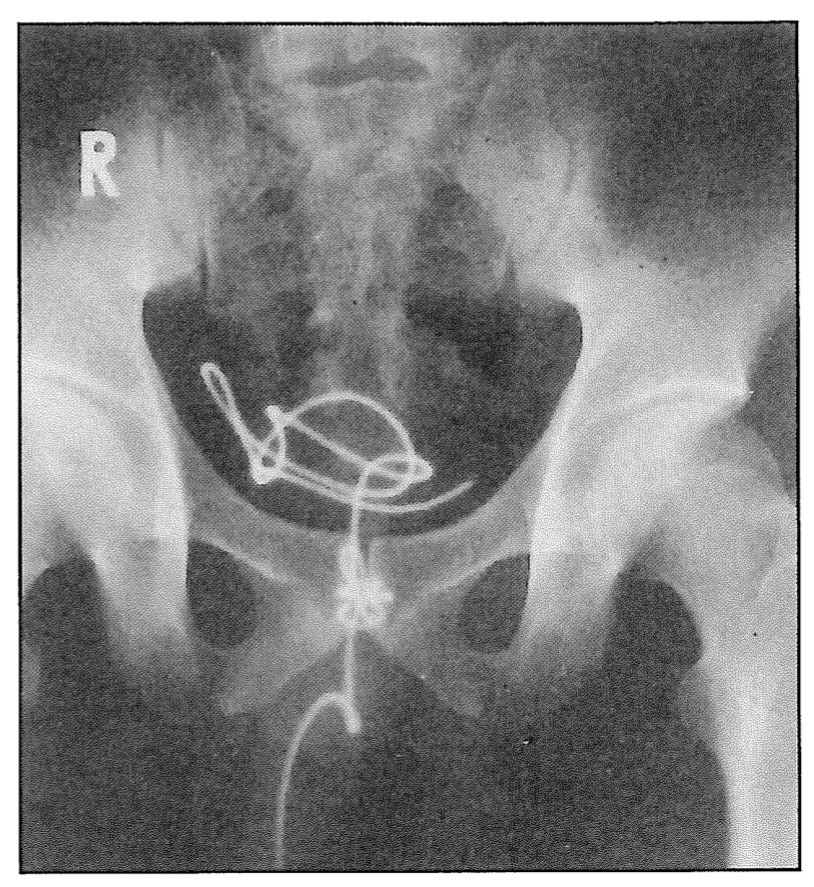

Пиявка в уретре

Пиявка в уретре 109 фото